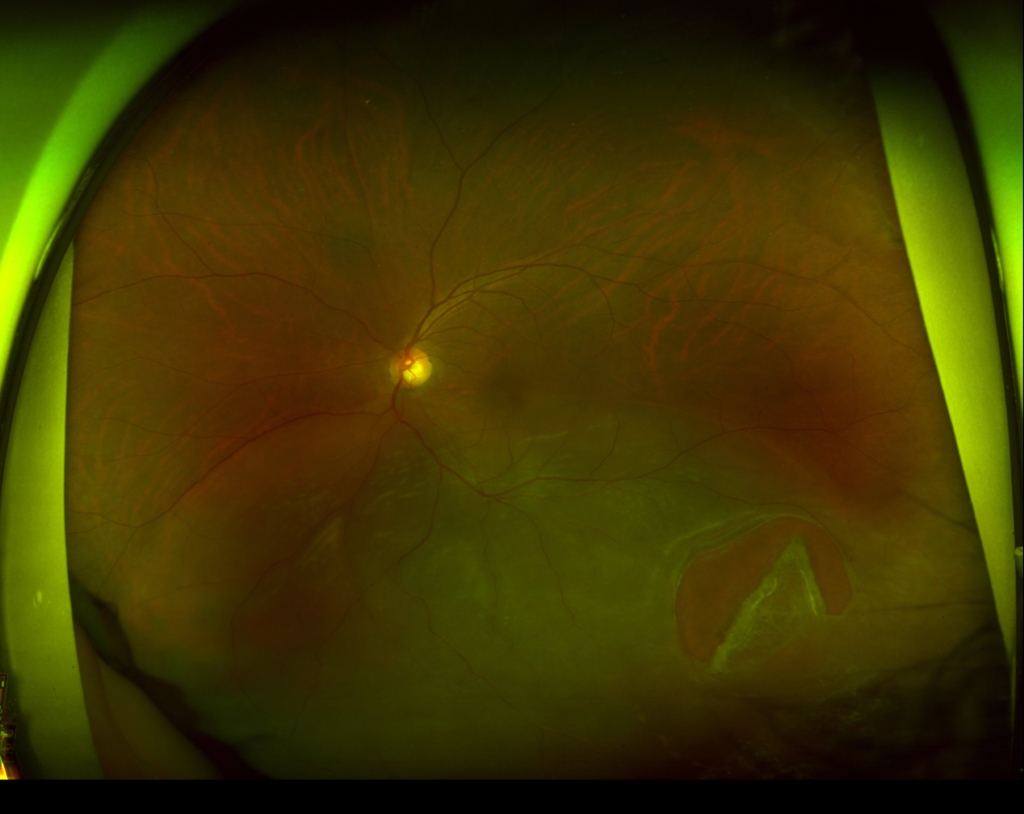

小口病

40歳 男性視力 右眼 0.02(1.2×-8.00) 左眼 0.04(1.2×-6.25=c-1.50A180°)主訴 検診で網膜色素変性症の疑いと指摘された。明らかな自覚症状なく、夜盲ははっきりしない。 金箔が剥げかかったような反射がみられる。 フラッシュERGで、減弱した...